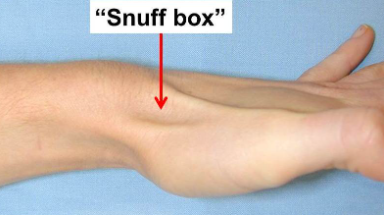

(1) 코담배갑부위 압통(Snuffbox tenderness)

-

- 코담배갑부위를 눌렀을 때 압통여부를 확인합니다.